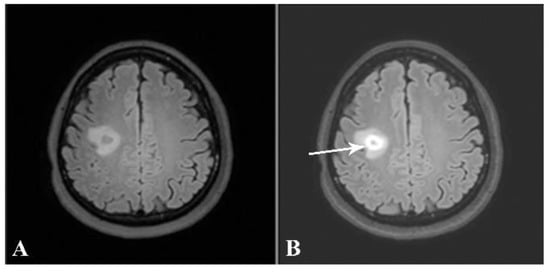

Taking into consideration each patient’s brain MRI and spinal MRI, if available, dissemination in space (DIS), according to the McDonald criteria, was found in 31 out of the 32 patients (96.9%). The only patient whose MRIs did not demonstrate DIS was the one with a brain MRI typical of tumefactive MS. The patient received a high dose of intravenous methylprednisolone. After follow-up, the lesion decreased in size and no new lesions were detected (Figure 8 and Figure 9).

Figure 8.

Axial precontrast FLAIR (A) and postcontrast FLAIR (B) images show complete ring-enhancing lesion (arrow) with minimal surrounding vasogenic edema. No significant pressure effect is shown. A presumptive diagnosis of small tumefactive MS was made, although there were no other lesions, either in the brain or in the spinal cord. The patient was given high-dose intravenous steroid.

Figure 9.

Follow-up axial postcontrast FLAIR images of the same patient after treatment with steroids at 2 and 6 months (A and B, respectively), showing decreased size of the lesion without residual enhancement.